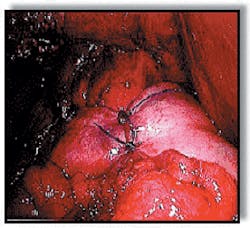

The operation used most often for GERD is called Nissen fundoplication (Figures 10-11).

- Fundoplication works by increasing pressure in the lower esophagus to keep acid from backing up.

- The surgeon wraps part of the stomach around the esophagus like a collar and tacks it down to provide more of a one-way valve effect.

- This procedure now can be done laparoscopically, without a large surgical incision. The surgeon makes a couple of very small cuts.

- This method leaves very little scarring and can produce a much faster recovery.

- Like all surgical procedures, fundoplication does not always work and can have complications.